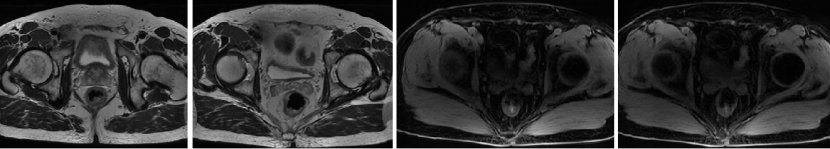

Q1 对于晚期转移性结直肠癌患者,目前,免疫治疗在新辅助治疗中的研究进展和临床应用如何? 结直肠癌是全球第三大肿瘤,转移性结直肠癌的5年生存率只有14%,治疗手段包括手术、化疗、放疗和靶向治疗等。免疫检查点抑制剂的出现也改写诊疗指南。大肠癌dMMR/MSI-H亚型约占所有病例的15%和mCRC病例的5%。由于dMMR/MSI-H的高突变率,肿瘤具有高免疫原性,使其能够激活免疫系统的抗肿瘤作用。 KEYNOTE-177这是一项三期国际开放标签随机对照研究,入选MSI-H/dMMR的IV期结直肠癌患者,比较帕博利珠单抗治疗(200 mg,每3周1次,最多35个周期)与在一线中使用或不使用抗VEGF或抗EGFR单克隆抗体的标准双药化疗,主要终点是PFS和OS。结果显示,帕博利珠单抗组患者的中位PFS时间为16.5个月 VS 8.2个月;3年PFS率分别为42% VS 11%,3年OS率分别为61% VS 50%。帕博利珠单抗组ORR为45.1%(20例完全缓解,49例部分缓解),化疗组为33.1%(6例完全缓解,45例部分缓解);帕博利珠单抗组83.5%的患者至少维持缓解了2年;在化疗组中,只有33.6%的患者缓解持续时间≥2年。KEYNOTE-177研究证实了帕博利珠单抗可以作为MSI-H或dMMR患者的一线标准治疗。 在2021版CSCO结直肠癌诊疗指南中,MSI-H结直肠癌姑息一至三线均推荐免疫治疗,其中帕博利珠单抗作为一线治疗的一级推荐;CheckMate-142研究选择MSI-H/dMMR转移性结直肠癌患者,单免后线vs双免后线vs 双免一线:ORR 39% vs 65% vs 71%,DCR 69% vs 81% vs 84%,一线双免完全缓解率为13%。结果说明双免好于单免,一线好于后线。CheckMate-142研究具有划时代意义,它将免疫治疗从后线前移到一线。 COMMIT研究是一项前瞻随机开放标签的三期临床研究,评估了阿特珠单抗单药治疗对比mFOLFOX6(氟尿嘧啶、奥沙利铂、亚叶酸钙)+贝伐珠单抗+阿特珠单抗一线治疗dMMR或MSI-H转移性结直肠癌的疗效和安全性,目前该试验还在进行中。未来该项研究的结果将回答对于MSI-H晚期结直肠癌,在一线免疫治疗的基础上联合化疗和抗血管靶向药物是否可以进一步提高免疫治疗的疗效。 CheckMate 8HW是另一项随机对照三期临床研究,在一线治疗dMMR或MSI-H转移性结直肠癌中,比较纳武利尤单抗单药、纳武利尤单抗联合伊匹木单抗以及研究者选择的化疗这3种方案的疗效。这项研究将头对头地比较对于MSI-H晚期结直肠癌双免联合是否优于单免的疗效。 Q2 对于MSI-H/dMMR型局部晚期结直肠癌(LACRC),新辅助免疫治疗探索的进展与应用前景如何?有哪些潜在预测疗效的生物标志物? 对于MSI-H/dMMR型局部晚期结直肠癌患者,新辅助免疫治疗可以在肿瘤手术前,提前使患者的免疫系统识别肿瘤细胞,从而使患者的免疫系统更好地产生免疫应答。目前结直肠癌新辅助治疗的探索均为二期研究,探索模式多为双免疫或免疫联合化疗方案,直肠癌多为免疫联合放化疗(同步或序贯)的模式。 NICHE研究是探索纳武利尤单抗联合伊匹木单抗用于Ⅰ-Ⅲ期结肠癌新辅助治疗的二期临床研究,研究共纳入40例结肠癌患者,其中21例为dMMR,20例为pMMR(1例患者同时为pMMR和dMMR),81%的dMMR患者和40%的pMMR患者为临床Ⅲ期结肠癌。患者在接受首次免疫治疗后不迟于6周内接受结肠癌手术,dMMR结肠癌缓解率100%,其中完全缓解的患者占60%,MPR为95%;pMMR治疗组27%的患者也对免疫治疗产生了良好的应答。 NICHE2研究,纳入更多患者,探寻非转移性dMMR结直肠癌患者双免治疗(伊匹木单抗+纳武利尤单抗)的疗效,主要终点为安全性,3年无病生存期。结果显示:MPR率95%,PCR率67%,中位随访13.1个月后没有患者出现疾病复发,毒性可耐受。 NCT04165772研究(前瞻性,单臂,Ⅱ期研究),Ⅱ期和Ⅲ期患者接受新辅助dostarlimab(多塔利单抗)共6个月,结果显示CCR率为100%。 PICC研究是特瑞普利单抗联合或不联合塞莱昔布新辅助治疗错配修复蛋白缺陷或微卫星高度不稳定的局部进展期结直肠癌的双臂随机Ⅱ期临床试验,结果显示完全缓解率高达88%,进一步表明dMMR结直肠癌免疫疗效惊人,潜在替代放化疗及手术。 对于MSI-H或dMMR结直肠癌,NCCN结直肠癌指南中,新辅助治疗增加纳武利尤单抗±伊匹木单抗或帕博利珠单抗单药方案;转化治疗可以选择双免疫或单免疫用药方案。 但并非所有患者都能从免疫治疗中获益,故筛选免疫治疗的疗效预测生物标志物将显得尤为重要。近年来研究主要集中在包括MSI-H、PD-L1过表达、TMB-H(TPS3645)、POLE或POLD1基因突变、PI3K/AKT/mTOR通路、新抗原(身份和数量)、免疫系统状态(免疫细胞特征、T细胞受体相关)等。 Q3 您如何看待对于临床中MSI-H/dMMR 转移性结直肠癌患者使用免疫治疗,部分患者仍然会出现耐药问题? Q4 晚期结直肠癌通常预后相对较差、患者生存期不长,依然是我国困扰结直肠肿瘤治疗的瓶颈问题,但有治愈的可能,此时临床医生制定正确合理用药方案尤为重要。今年上半年发布的CACA-RC指南推荐不适合强烈治疗患者应用曲氟尿苷替匹嘧啶片(TAS-102)联合贝伐珠单抗,作为晚期不可切除结直肠癌姑息一线治疗方案。请您谈谈该推荐治疗对我国晚期不可切除结直肠癌患者的临床治疗带来怎样的获益? 今年上半年CACA-RC指南推荐了不适合强烈治疗的患者应用TAS-102联合贝伐珠单抗作为不可切结直肠癌一线治疗方案,是在不可切除晚期结直肠癌一线治疗中石破天惊的一项突破。晚期mCRC的标准化疗方案在指南中是以奥沙利铂或伊立替康为基础的FOLFOX和FOLFIRI方案,在此基础上,可以根据基因分型联合西妥昔单抗或者贝伐珠单抗,但是依旧有部分患者身体状况无法耐受加强化疗,针对这一类患者的治疗方案选择非常有限,且预后情况并不理想。TAS-102+贝伐珠单抗治疗方案毒副反应相对较低,(临床试验提示比贝伐珠单抗联合卡培他滨效果好)疗效确切,在未来较长一段时间内,尤其是目前疫情肆虐,患者不方便住院治疗时,TAS-102可作为国内不适合强烈治疗的mCRC患者及老年患者的一线治疗优选方案,并为患者带来持续的、更优的生存获益。 二 病例分享 专家简介 王峰 教授 医学博士,副主任医师,硕士研究生导师 滨州医学院附属医院肿瘤科副主任 澳大利亚悉尼维斯迈医学中心访问学者 中华医学会放射肿瘤治疗学分会骨与软组织学组委员 中国临床肿瘤学会(CSCO)神经系统肿瘤专家委员会委员 山东省医师协会肿瘤精准医疗医师分会常务委员 山东省医师协会肿瘤放疗医师分会委员 山东省抗癌协会消化道肿瘤分会常务委员 山东省医学会咽喉肿瘤多学科联合委员会委员 山东省医学会烟草病学与戒烟多学科联合委员会委员 山东省健康管理协会消化道肿瘤防治分会常务委员 山东省医学会放射肿瘤学分会青年委员 山东省医学会妇科肿瘤多学科联合委员会委员 滨州市医学会放射肿瘤学专业委员会副主任委员 01 基本情况 (一)基本信息 患者男性,65岁,于2021-08-26第一次入滨州医学院附属医院风湿免疫科。 主诉:发作性右踝关节肿痛3年,再发1月。 查体:双足第一跖趾关节可见红肿,伴局部皮温升高。 既往史、个人史:既往脑梗死病史7年余,未遗留后遗症;有“膀胱结石”病史1年余,未系统诊治;有“痛风性关节炎”3年余,曾于滨州医学院附属医院风湿免疫科治疗。有高血压病史10年余,最高血压180/110mmHg,口服“吲达帕胺片”,血压控制可。 常规检查发现2次大便潜血阳性。 (二)辅助检查结果 1.肠镜检查 直肠、乙状结肠:直肠距肛门7cm可见一巨大溃疡型病变,表面溃烂,污秽苔,周边环堤样隆起,累及管腔1/3周圈,管腔无狭窄,于病变周边多点活检8块,质脆易出血;乙状结肠见一0.5cm*0.3cm息肉,余黏膜光滑,皱襞清晰,蠕动规律;肛管未见异常。降结肠、横结肠:横结肠见一0.3cm*0.4cm 0-IIa型息肉,表面粗糙,余黏膜光滑,血管纹理清晰,未见异常。 诊断:1.直肠Ca(进展期 溃疡型);2.结肠多发息肉——内镜下冷切除术+息肉摘除术。 2.胸部、上腹部未见明显异常。 直肠MR增强+DWI:直肠距肛缘约5.5cm处肠壁明显不均匀增厚,累及长度约6.0cm,呈等/长T1、等/稍长T2信号,T2压脂呈不均匀高信号,DWI呈高信号,ADC图信号减低,增强扫描呈明显不均匀强化,相应局部管腔狭窄,邻近浆膜面模糊,周缘可见小淋巴结。 02 治疗经过 2021-09-08:于全麻下行全直肠系膜切除+末端回肠预防造瘘术。 术中见:肝脏、胃、腹壁等无转移性结节。肿块位于腹膜返折处,活动度差,侵及浆膜。肠周见明显散在肿大淋巴结。 术后病理:直肠下段中分化腺癌,侵犯外膜下脂肪组织,肿瘤出芽分级(高级别,Bd3),侵犯神经侵犯,未见确切脉管内癌栓;两侧手术切缘、环周切缘及标记切缘内均未查见癌累及,肠周淋巴结内未查见转移癌(0/17)。pTNM分期:pT3N0Mx。免疫组化结果:CK(+),MSH2(+),MSH6(+),MLH1(+),PMS2(+),MDR-1(3+),HER2(3+),P53(3+),Ki-67阳性率约70%。 术后诊断: 1.直肠癌II(pT3NOMO)期术后; 2.结肠多发息肉术后; 3.痛风性关节炎; 4.高血压病(3级 很高危); 5.脑梗死。 CSCO指南: 2021-10-04至2022-06-03:FOLFOX方案化疗10周期(奥沙利铂150mg d1+氟尿嘧啶 0.7g d1+4.4g civ);术后预防性放射治疗DT5000cGy/25f,同步卡培他滨。 2021-11-25至2021-12-06:尿培养提示肺炎克雷伯菌感染,结合泌尿外科、感染科会诊意见,给予左氧氟沙星抗感染治疗。 2022-06-12 肺无法穿刺活检。 基因检测示:(直肠)KRAS/BRAF/NRAS/PIK3CA 基因均未检出突变。伊立替康UGT1A1基因检测结果:非风险基因型。 CSCO指南: 2022-06-20:西妥昔单抗联合FOLFIRI方案治疗(西妥昔单抗900mg d1,伊立替康320mg d1,氟尿嘧啶0.7g iv 4.3g civ)。 2022-07-06:骨髓抑制、腹泻,西妥昔单抗联合FOLFIRI方案治疗(西妥昔单抗900mg d1,伊立替康280mg d1,氟尿嘧啶0.7g iv 4.3g civ)。 疗效对比: 循证依据: C-TASK FORCE研究:首个证实TAS-102联合贝伐珠单抗治疗mCRC的疗效及安全性研究。TAS-102联合贝伐珠单抗是难治性mCRC患者潜在治疗选择,更多临床获益有待进一步研究。 TAS-102联合贝伐珠单抗治疗mPFS时间和mOS时间分别为5.6个月和11.2个月。 TAS-102联合贝伐珠单抗不良反应主要为血液学毒性。 日本大样本RWS:TAS-102和瑞戈非尼不同排序的回顾性研究。 日本大样本RWS:TAS-102单药较瑞戈非尼单药,可显著延长mOS,降低AE。 日本大样本RWS:两药序贯疗效优于单药,且≥65岁先用TAS-102获益更显著。 日本大样本RWS:TAS-102序贯瑞戈非尼组持续治疗时间更长。 2022-07-27至今 给予贝伐珠单抗联合TAS-102治疗期间复查CT评估SD,胃肠道反应不重,骨髓抑制Ⅰ度,耐受性尚可。 *本文仅代表专家观点,并经专家审校。